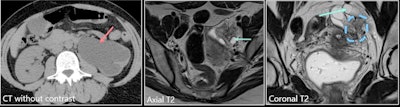

The ureter is a common site of urinary tract endometriosis. It originates from adjacent disease of the ovary, broad ligaments, or uterosacral ligaments, and presents as irregular hypointense nodules on T2-weighted images. Extrinsic disease may be suspected when the interface of fat between the nodule and ureter is no longer visible. It is really important to mention it to the surgeon, and it may require the presence of a urologist during the procedure, the authors emphasized.

Involvement of the different ureteral layers is very difficult to determine on imaging. Also, endometriosis symptoms may be secondary to upper urinary tract involvement (flank pain, obstruction), and always check for ureteral and or renal dilation (risk of renal failure if untreated)